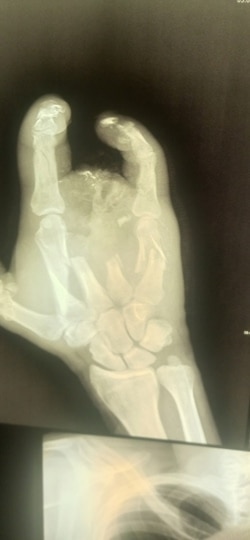

– Как меня вытащили, как везли до полевого госпиталя – не помню ни черта. Очнулся, узнал, что получил осколочное ранение, обжег шею, глаз, невзрывное осколочное ранение оторвало мне полруки, снесло все пальцы, разгромило всю кисть. Увезли меня в Луганск, там позволили три недели полежать, и все. Выпнули из военного госпиталя в обычную больницу. Я еще удивился, зачем на последние пять дней. Потом узнал.

Рука Алексея после ранения на войне

Оказалось, что с незажившими ранами покалеченного солдата отправили в гражданское медучредждение для того, чтобы на руках у него не было документов из военного госпиталя. И сейчас Алексей не может доказать, что стал калекой в бою.

– Прописали мази и перевязки. Я засомневался, что лечение нормальное, благо, был знакомый хирург. Я пришел к нему и очень вовремя – началось загноение на обрубке руки. Там он уже сделал все заново – чистка, вставил спицы и даже часть кости восстановить смог. Конечно, все за деньги. Всю "зарплату", что получил за войну, считай, все на хирурга и ушло! В итоге вышел "в минус", – подытоживает Алексей.